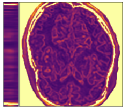

Figure 5 shows an example of a spatio-temporal regularization parameter-map which was estimated using the proposed approach for an acceleration factor of . The network estimates the regularization parameter-map to be pointwise relatively consistenly higher than the spatially required regularization. This result is in fact expected as the temporal dimension is the one for which the gradients of the images are the sparsest because of the high temporal correlation. Further, we see how the network consistently predicts both the spatial regularization as well as the temporal regularization to be less strong in the area where most of the movement is expected, i.e. in the cardiac region.

Figure 6 shows examples of the quantitative (magnitude) images of three of the 112 simulated inversion recovery measurements in the test dataset. We also show the regularization parameter-maps for regularization along the spatial directions and along the inversion-time direction generated by the network. The mean PSNR and SSIM of our proposed method is consistently higher for all considered acceleration factors, even compared to PDHG with regularization strength along spatial and inversion-time direction chosen by grid-search with access to the ground truth images (shown in Figure 8 and Table 2). The resulting parameter-maps after performing the regression on the reconstructed images are shown in Figure 7. Again, our proposed method results in the lowest RMS deviation from the ground truth images (Table 2).